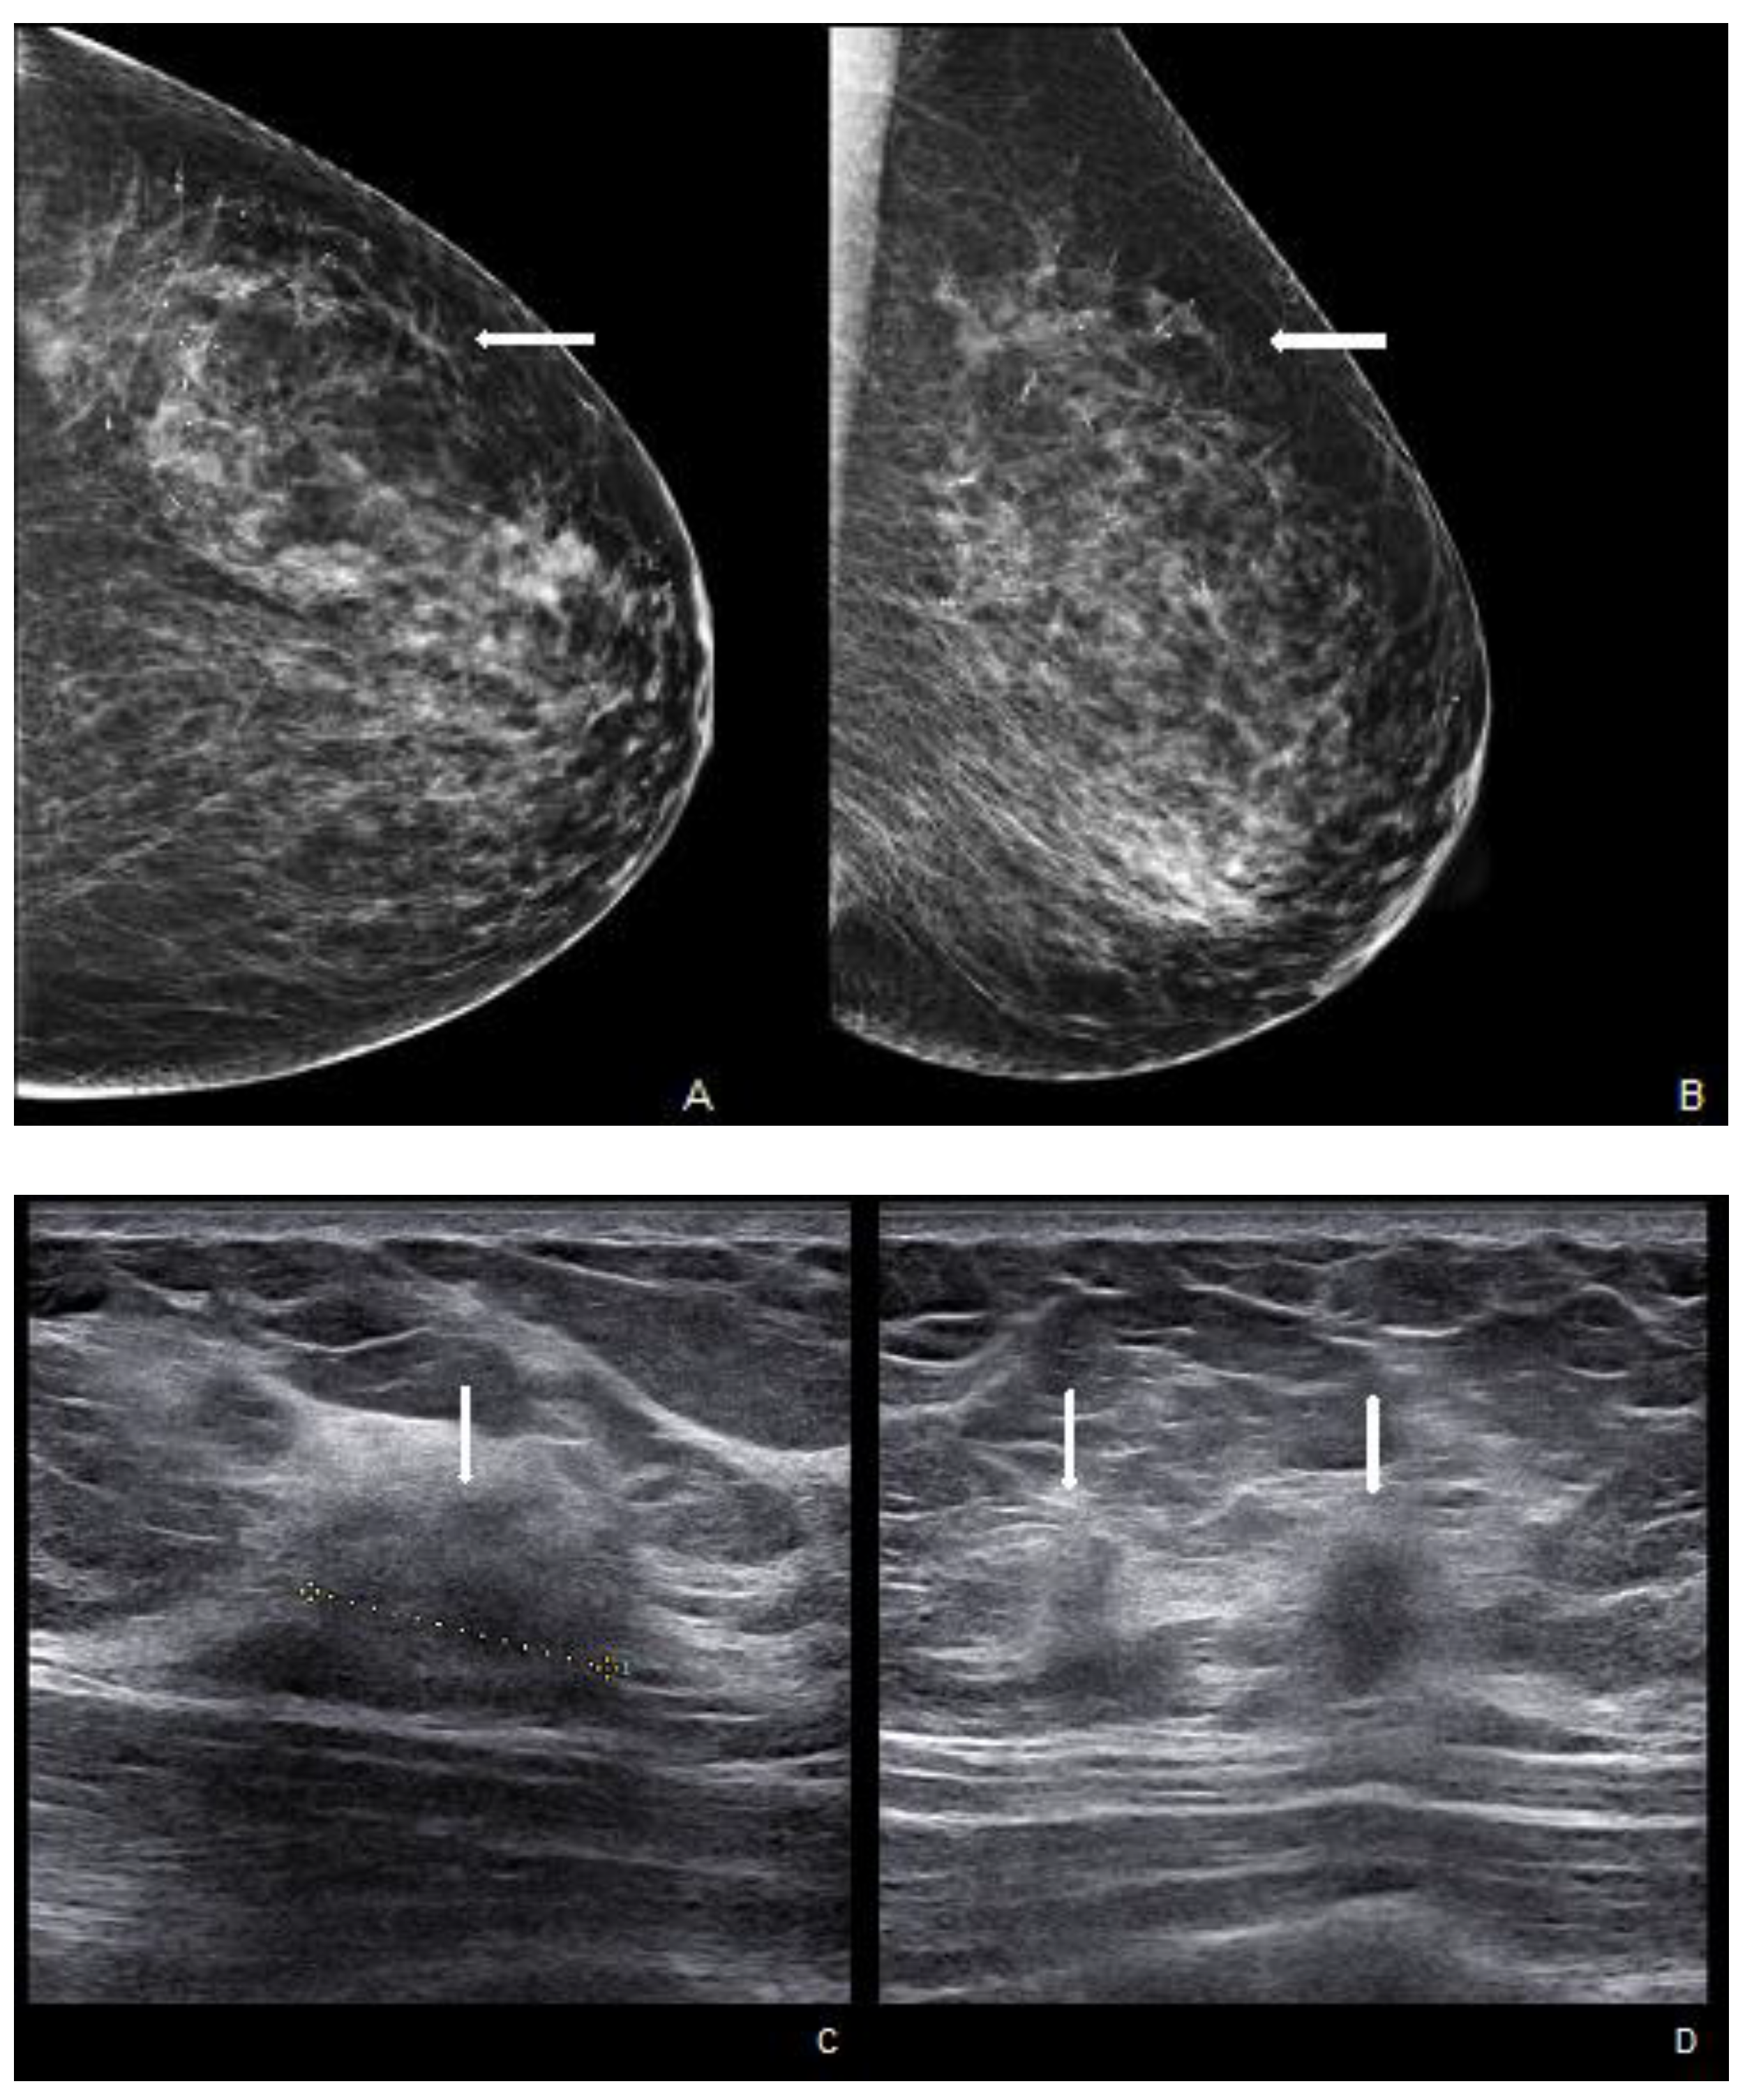

Figure 6.

Woman with a palpable mass of the outer left quadrants and a history of pruritic erythema of the ipsilateral nipple. A skin biopsy was performed with PC positivity. Unilateral craniocaudal (A) and oblique (B) mammograms of the left breast show diffuse fine pleomorphic microcalcifications (arrow) in the upper outer quadrant with architectural distortion associated. US detects multiple inhomogeneous hypoechogenic areas (arrow) with poorly defined margins and maximum diameter of 15 mm (yellow line) (C,D), corresponding to foci of non-mass-like enhancement with associated nipple enhancement (E,F). The patient underwent a left mastectomy, and high-grade invasive e multicentric ductal carcinoma was diagnosed.

US is a non-invasive, repeatable, and widely available technique. Its inclusion in the initial assessment could benefit and warrants consideration, mainly when DM yields negative results, especially in women with denser breast tissue. Similar to mammographic MPD findings, US alterations are nonspecific and include expected changes for BC treatments, including hypoechogenic masses, microcalcifications, ductal ectasia, NAC flattening, asymmetry, and thickening [26,47,48] (Figure 5). Additionally, US offers an option of immediate image-guided intervention and improves the diagnostic accuracy for axillary lymph node status. However, not all underlying BC can be identified through the US. MRI’s higher sensitivity in evaluating the retroareolar region provides crucial information for clinically evident MPD cases with occult findings in DM and US and for the preoperative assessment of disease extent in patients eligible for breast-conserving therapy [26,47]. In addition, thanks to contrast enhancement, it shows nipple involvement [49]. MRI findings include asymmetric and abnormal NAC enhancement patterns, sometimes associated with non-mass-like enhancement or suspicious masses elsewhere in the breast [26,47,50], even a distant site with no apparent anatomic connection, about possible MPD multifocality and multicentricity (Figure 6). MRI may also evaluate lymph node status, raising concerns about axillary or internal mammary involvement. However, it is essential to note that false-negative MRI results for NAC evaluation in MPD cases have also been reported [25,50], probably for less-aggressive disease forms. Therefore, all clinically suspicious findings must undergo biopsy, regardless of negative imaging results. A full-thickness NAC biopsy with histological and immunohistochemical evaluation is the gold standard for establishing an ultimate diagnosis [38]. Research examining the molecular markers in MPD cases has revealed an expression of HER-2/neu, cytokeratin 7 (CK7), mucin 1 (MUC1), and human milk fat globule, and positive staining with CAM 5.2 antibody [51,52]. Exfoliative cytology with PC demonstration may be helpful, but a negative result can occur; its use has been postulated as an easy screening test for eczematous skin changes to the nipple.